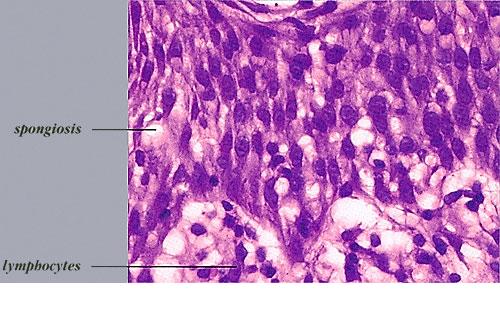

Acute contact dermatitis = التهاب ا لجلدالحاد بالتماس